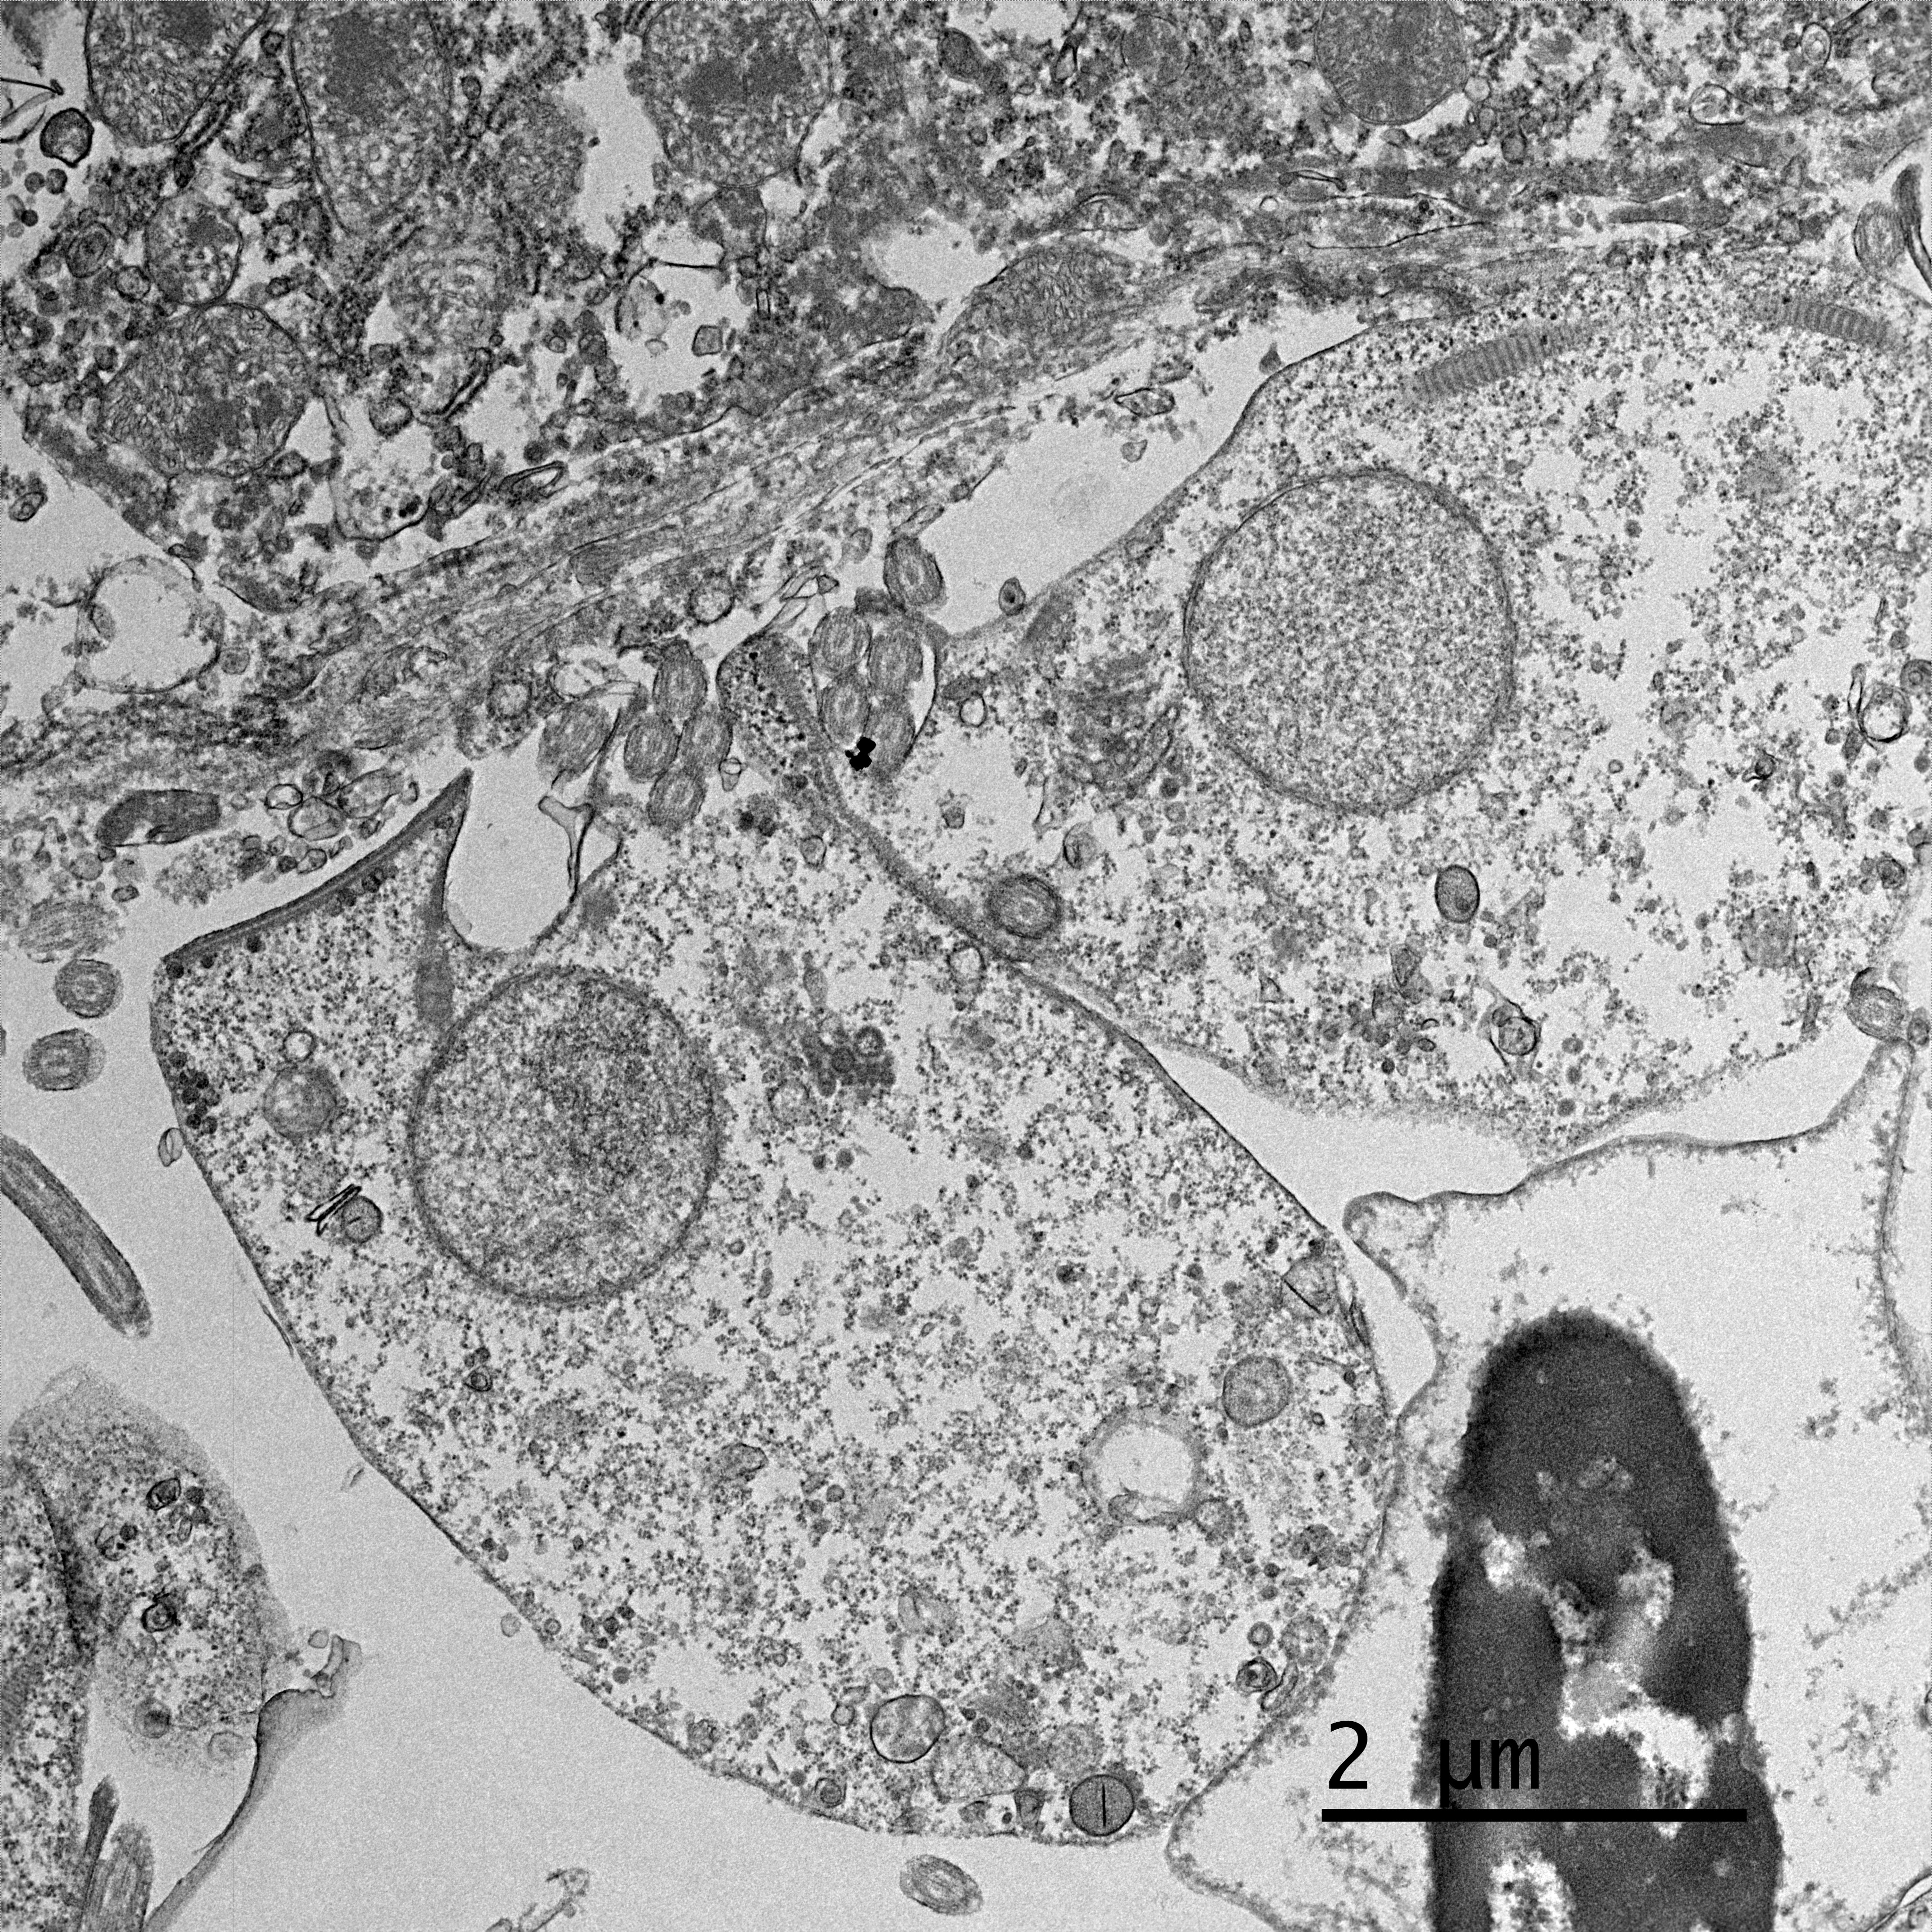

Electron microscopy, California Animal Health and Food Safety Lab in Davis, CA (formalin-fixed liver):

- Free organisms- family Trichomonadidae flagellates with 5 apical flagella (one recurrent)

- Lymphocytes- Intracytoplasmic Isospora

Present in often very large numbers throughout the vasculature were extracellular protozoa consistent with flagellates that could have contributed to the inflammation in some tissues. Using a trichomonad PCR assay, sequences with a closest match to Cochlosoma anatis were obtained from both lung and intestine, although identity was only ~93%. Electron microscopy of liver tissue confirmed intracellular protozoa consistent with Isospora, and extracellular flagellates consistent with tetratrichomonads based on the presence of 5 undulipodia at the apical pole with one recurrent. In contrast, Cochlosoma sp. have six flagella, one of which is recurrent. Both Cochlosoma and Trichomonas have a single nucleus, a parabasal apparatus, a tubular axostyle, and a crescent-shaped pelta.6 Prior studies have identified via sequence analysis of the 16S rRNA gene that Cochlosoma and Trichomonas are genetically similar, which likely accounts for the 93% identity match.4Tetratrichomonas and C. anatis are often identified with other intestinal pathogens and their pathogenicity as a sole pathogen remains uncertain.1,4 Both have been documented as the cause of fulminant disease in a variety of birds. Tetratrichomoniasishas been identified as the causative agent of acute typhlohepatitis in ducks, a necrotizing hepatitis and splenitis in a Waldrapp ibis and necrotizing hepatitis in a free-ranging white pelican.1,2Cochlosoma anatis is linked to enteritis in turkeys, as well as increased dehydration, malabsorption, and mortality in young finches.4 However, prior studies have failed to document clinical signs or histologic lesions in experimental infections with Trichomonas and coinfections of Cochlosoma with other intestinal pathogens have demonstrated greater pathogenicity than with either pathogen alone.1,4

Finally, Dr. Pesavento quizzed participants on the ultrastructural images from this case, which was an appreciated, succinct review for many attendees. Key takeaways from this discussion included trusting your anchors (i.e. erythrocytes, nuclei, etc.), determining the number of cell profiles in the EM image, and knowing what normal looks like so you can evaluate the abnormal. The protozoal organisms on EM had some key characteristics to look for, as well, including the flagella on the Trichomonads with their classic microtubule 9+2 arrangement, and the apicomplexan conoid, rhoptries, and micronemes within the Isospora.5,6 Her last piece of wisdom in this case regarded microvilli on EM: don't call them microvilli unless you can see the actin microfilaments holding them up. If not, they are termed "cellular projections."